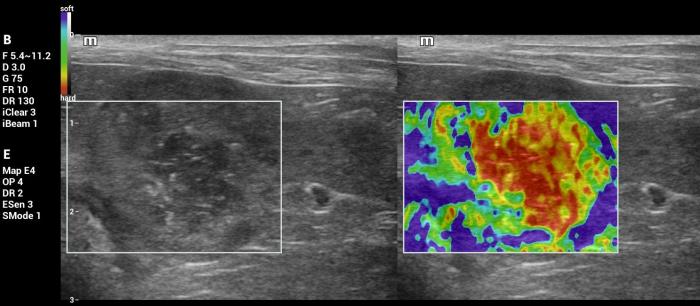

Hallazgos elastográficos (Natural Touch Elastography®): el nódulo presentó una rigidez marcadamente aumentada respecto del parénquima esplénico circundante, con patrón elastográfico heterogéneo (“dureza mixta”), caracterizado por áreas internas de elevada velocidad de onda de corte (Figura 26-27).

Este comportamiento se alinea con los hallazgos reportados para lesiones malignas esplénicas, que tienden a presentar valores superiores a 3 m/s según la evidencia publicada5.

Las mediciones fueron consistentes entre sí y no mostraron artefactos relevantes, lo que respalda la confiabilidad del hallazgo elastográfico.

Interpretación:la combinación de ecogenicidad mixta, presencia de focos hiperecoicos puntiformes, deformación esplénica y vascularización positiva plantea un patrón ecográfico compatible con neoplasia. La rigidez significativamente elevada respecto del parénquima esplénico normal constituye un hallazgo congruente con lesiones malignas, tal como se ha documentado en estudios previos5.

En este caso, el comportamiento elastográfico resultó altamente concordante con el diagnóstico final de linfoma folicular, reforzando la utilidad de la elastografía mediante NTE para apoyar la sospecha diagnóstica en el contexto de masas esplénicas sólidas.